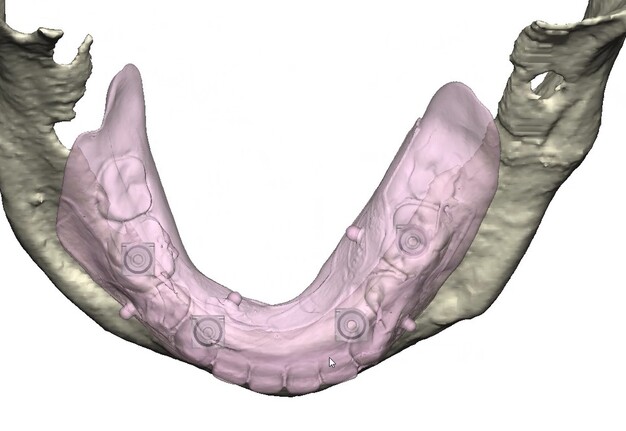

Records for this patient were collected using a dual-scan CBCT and intraoral scanning. A surgical planning session was completed with KLS Martin for the fabrication of a CAD-CAM subperiosteal implant system with immediate loading of a mandibular prototype (Figs 2-5).

A 3D-printed mandibular model with the subperiosteal system and prototype in place was also fabricated (Figs 6 and 7).